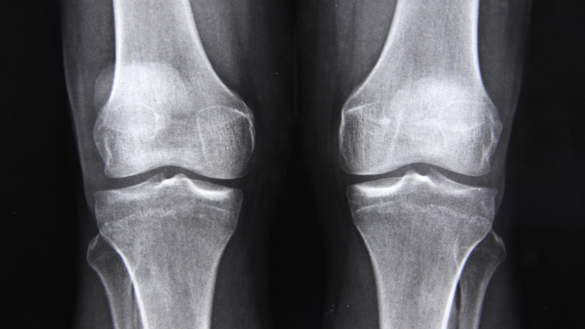

Benskörhet (osteoporos): symtom, risker & behandling

Det sker runt 70 000 benbrott efter fall, per år i Sverige. Den största orsaken är minskad benmängd, vilket kan ge benskörhet – osteoporos. Docent Thomas Kjellström beskriver varningssignaler för ökad risk för benskörhet och det finns även tips om ett test man kan göra själv.

Benskörhet kan orsaka långvarigt lidande

Benskörhet är en vanlig åkomma hos kvinnor efter klimakteriet. Många drabbas av skelettskador med smärta, funktionshinder och nedsatt livskvalitet som följd. Värst är frakturer på ryggkotor som ger ett mycket långvarigt lidande, visar en doktorsavhandling vid Linköpings universitet.